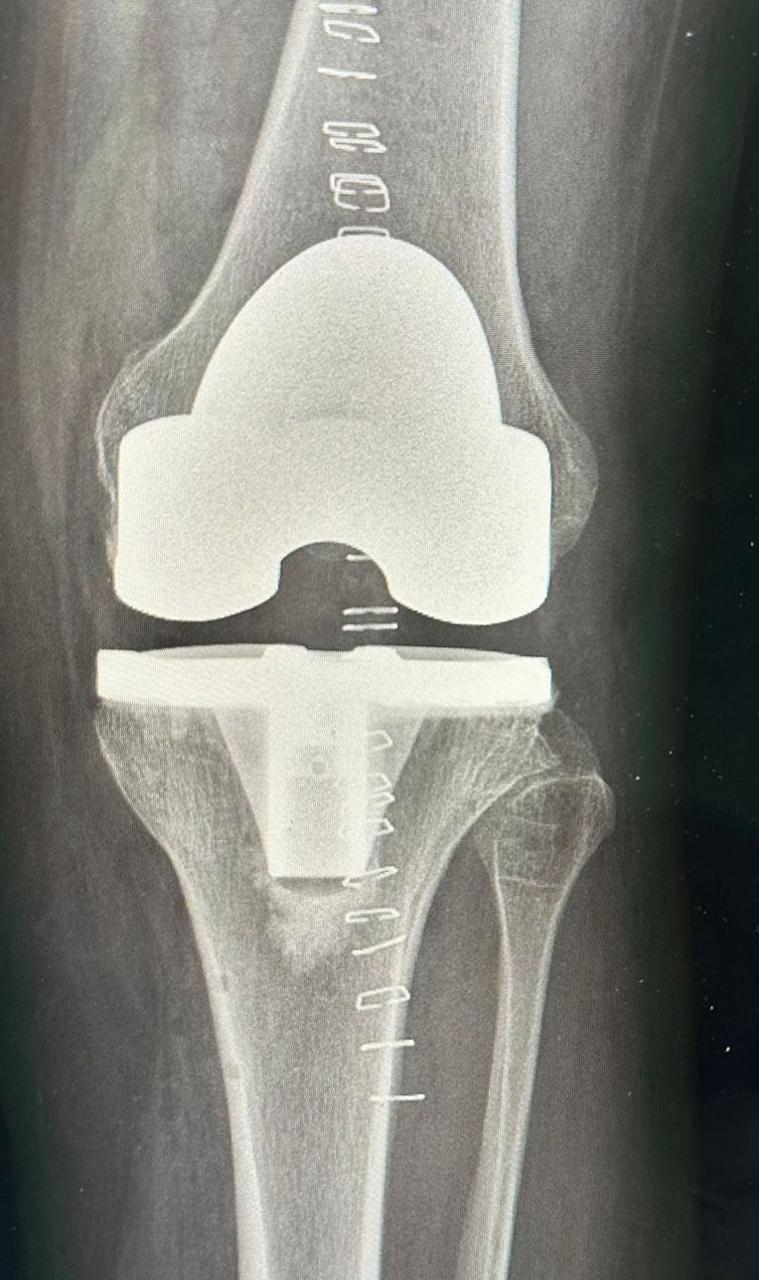

بتقنية الروبوت… مستشفى الدرعية يجري عملية دقيقة لاستبدال مفصل الركبة لمريضة تبلغ 46 عامًا Admin 25/01/2026 المزيد

برنامج علاجي متكامل يعيد الحركة لمراجع بعد جراحة استبدال مفصل الركبة في مستشفى الدرعية Admin 13/01/2026 المزيد

مركز التميز لجراحات المفاصل الصناعية بمستشفى الدرعية يحقق تقدّمًا نوعيًا في خدمات استبدال المفاصل Admin 22/12/2025 المزيد